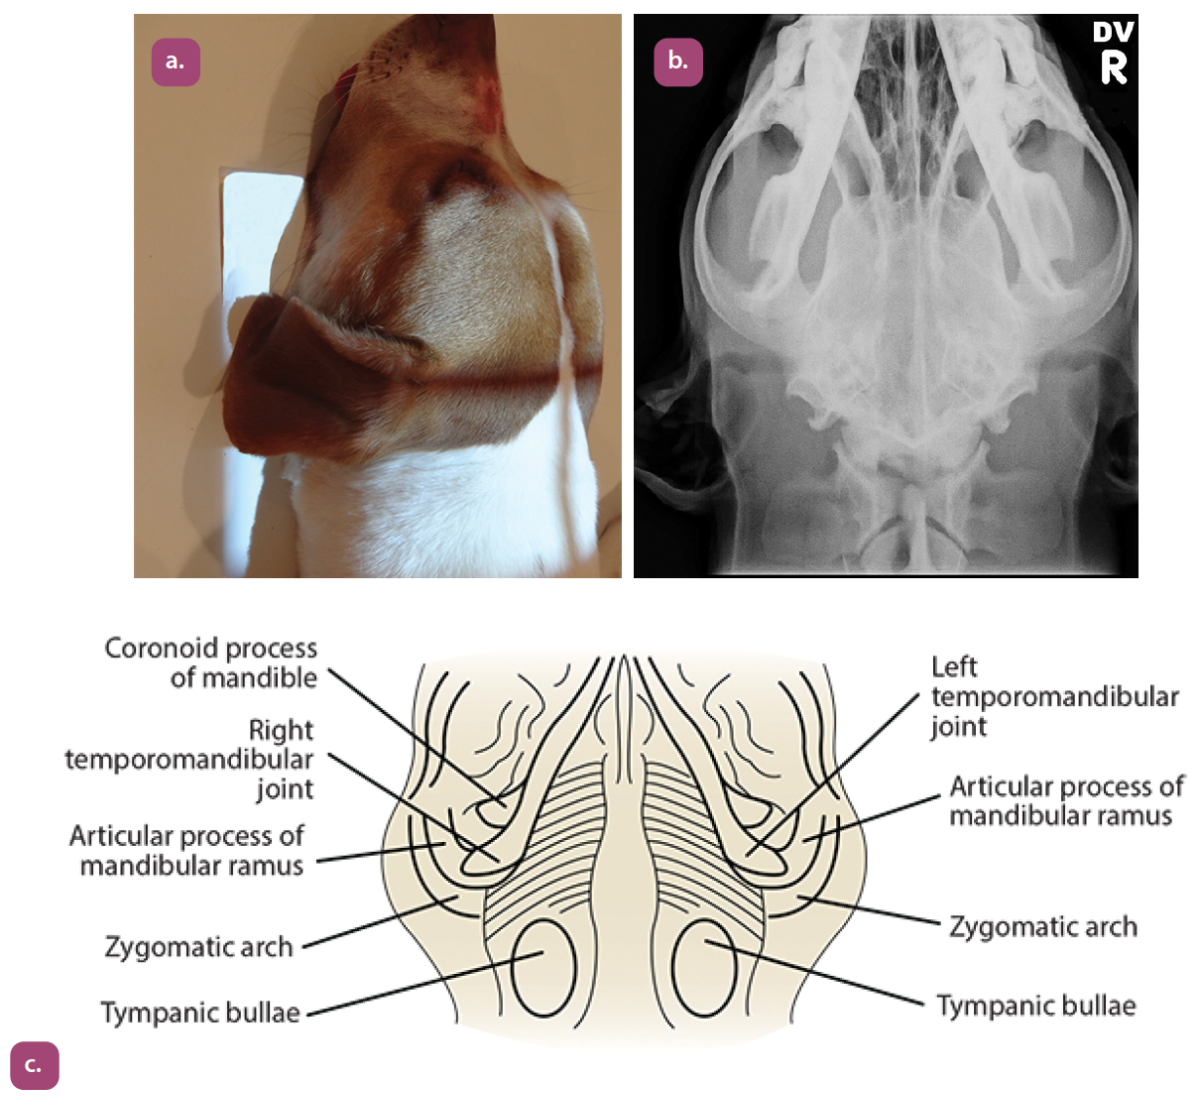

dorsoventral temporomandibular joint projection